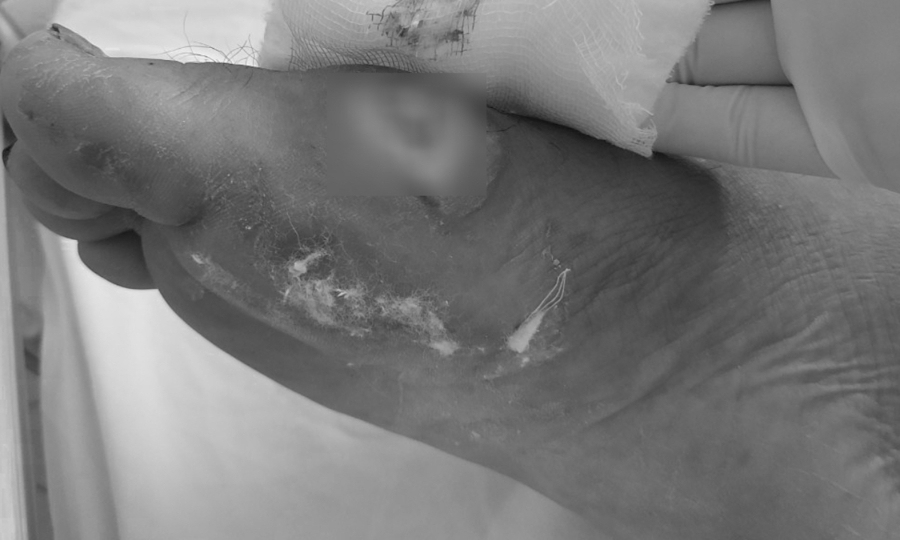

Hoại tử do vi khuẩn Burkholderia ở chân bệnh nhân. Ảnh: Bệnh viện cung cấp.

Sau đợt bão lũ kéo dài từ đầu tháng 10 đến nay, nhiều trường hợp mắc bệnh Whitmore đã gia tăng ở nhiều tỉnh miền Trung. Quảng Trị ghi nhận 24 ca, Bệnh viện Thừa Thiên-Huế tiếp nhận 30 ca … Bệnh viện Đà Nẵng điều trị 29 ca, bệnh nhân chủ yếu đến từ Quảng Nam, Nghệ An, Quảng Ngãi và Đà Nẵng. – Vết thương do áp xe do Whitmore gây ra đã được điều trị. Ảnh: Bệnh viện cung cấp.